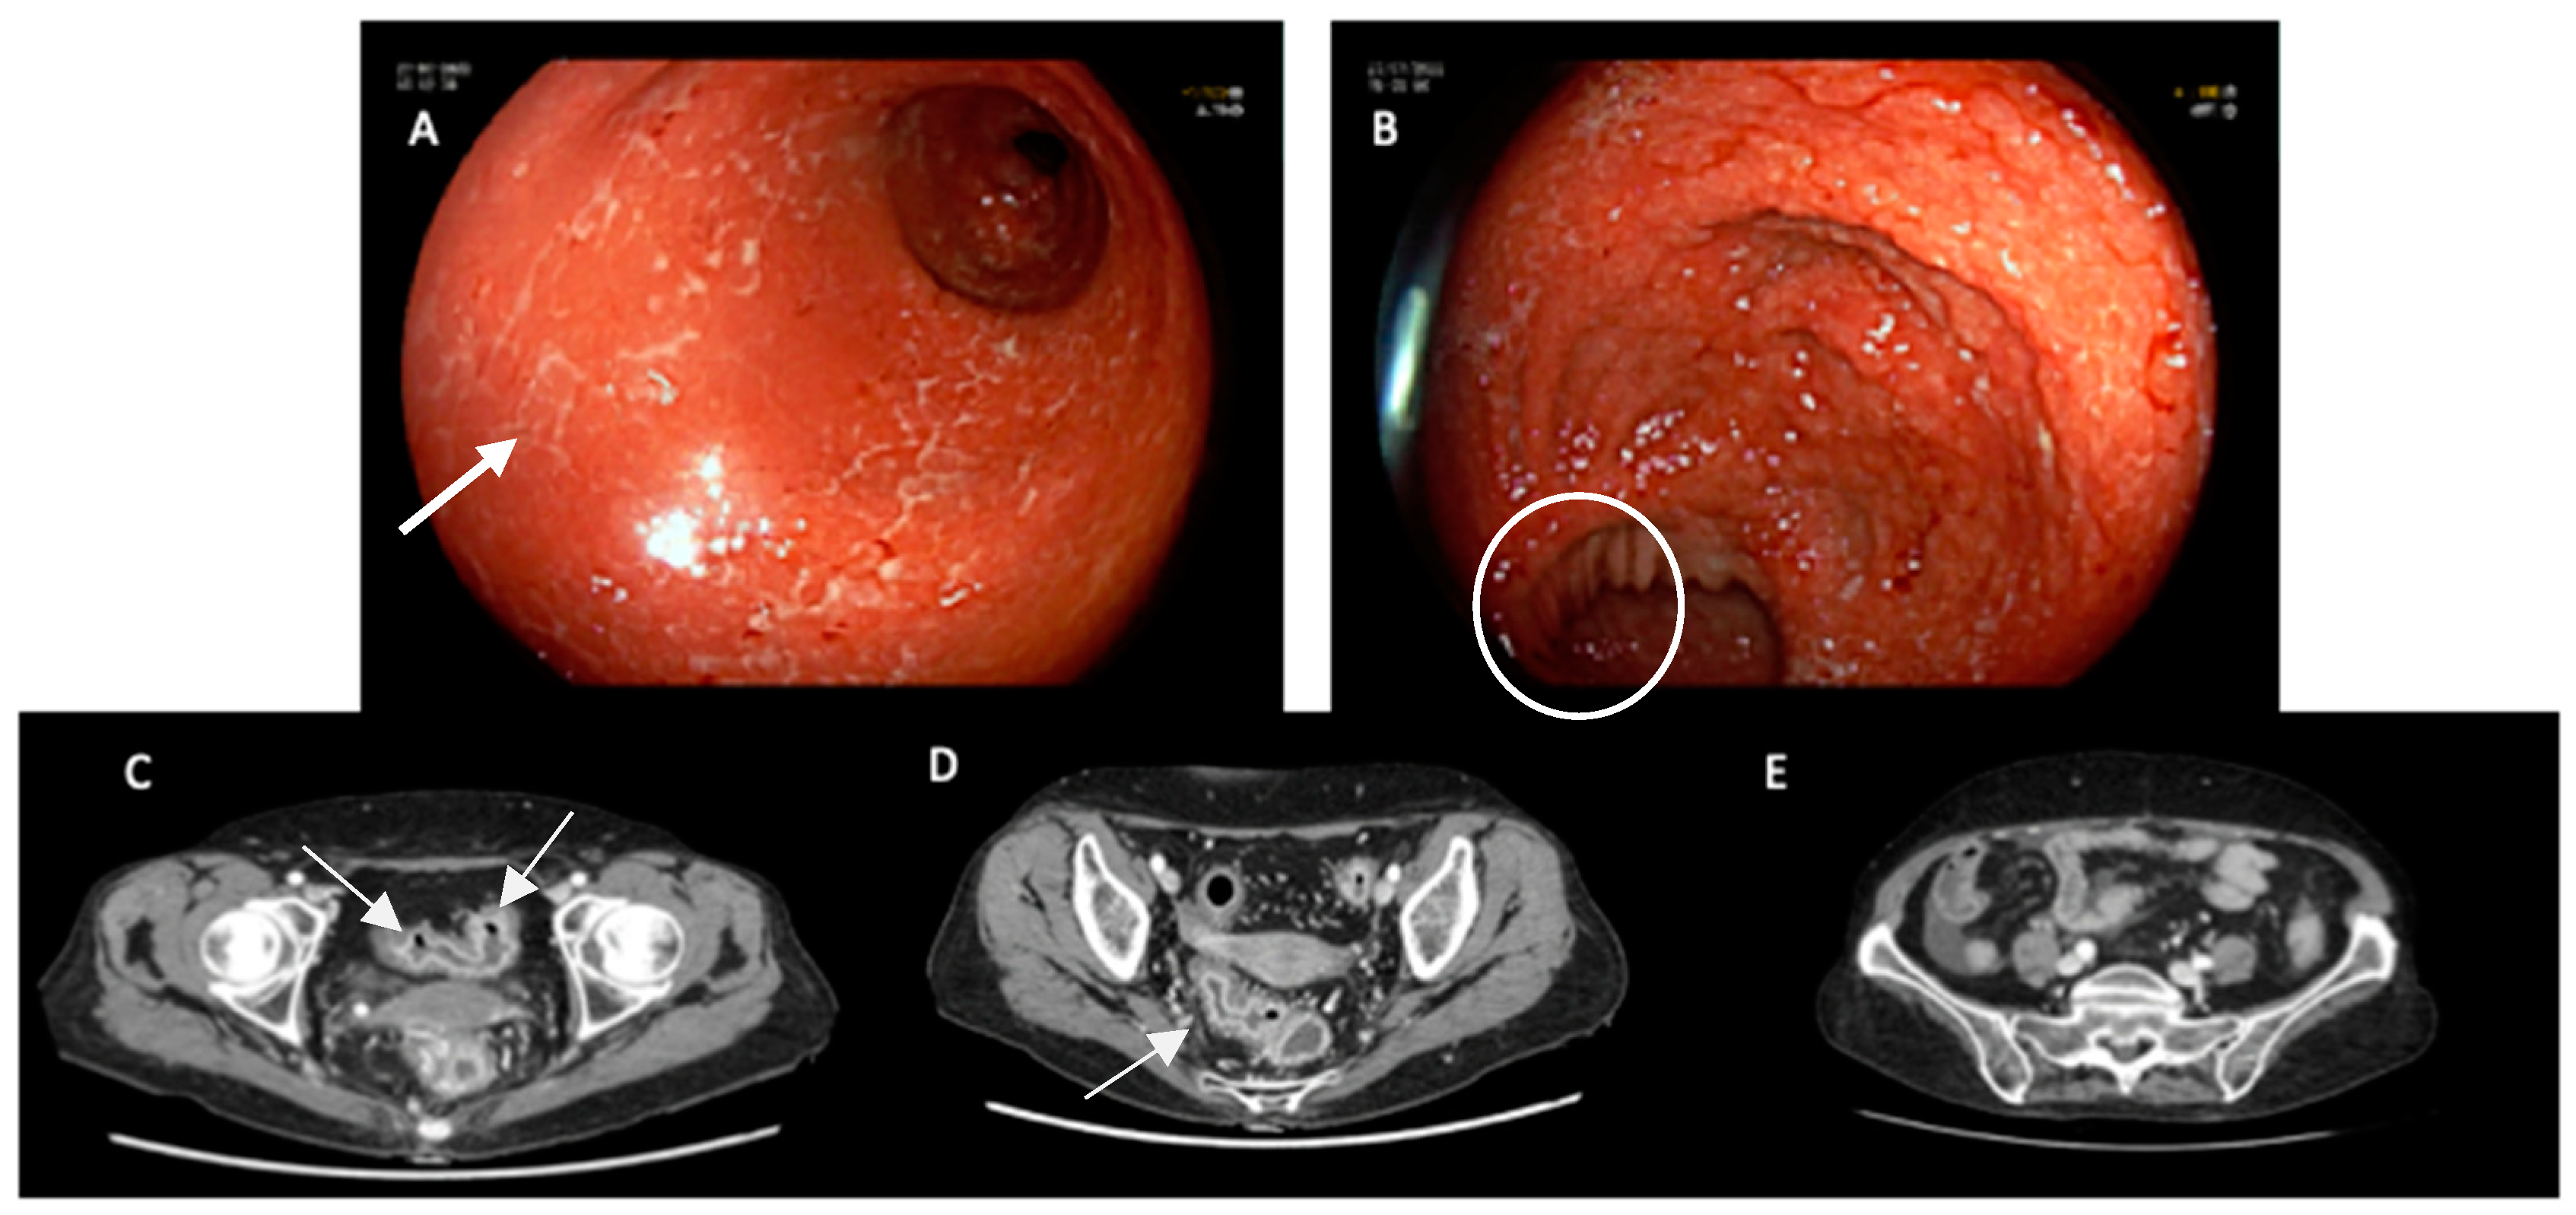

4.3. Imaging

- Gosangi, B.; McIntosh, L.; Keraliya, A.; Irugu, D.V.K.; Baheti, A.; Khandelwal, A.; Thomas, R.; Braschi-Amirfarzan, M. Imaging features of toxicities associated with immune checkpoint inhibitors. Eur. J. Radiol. Open 2022, 9, 100434. [Google Scholar] [CrossRef]

- Barina, A.R.; Bashir, M.R.; Howard, B.A.; Hanks, B.; Salama, A.; Jaffe, T.A. Isolated recto-sigmoid colitis: A new imaging pattern of ipilimumab-associated colitis. Abdom. Imaging 2015, 41, 207–214. [Google Scholar] [CrossRef]

- Garcia-Neuer, M.; Marmarelis, M.E.; Jangi, S.R.; Luke, J.J.; Ibrahim, N.; Davis, M.; Weinberg, J.; Donahue, H.; Bailey, N.; Hodi, F.S.; et al. Diagnostic Comparison of CT Scans and Colonoscopy for Immune-Related Colitis in Ipilimumab-Treated Advanced Melanoma Patients. Cancer Immunol. Res. 2017, 5, 286–291. [Google Scholar] [CrossRef]

- Shieh, A.C.; Guler, E.; Pfau, D.; Radzinsky, E.; Smith, D.A.; Hoimes, C.; Ramaiya, N.H.; Tirumani, S.H. Imaging and clinical manifestations of immune checkpoint inhibitor-related colitis in cancer patients treated with monotherapy or combination therapy. Abdom. Imaging 2019, 45, 3028–3035. [Google Scholar] [CrossRef]

- Durbin, S.M.; Mooradian, M.J.; Fintelmann, F.J.; Zubiri, L.; Chute, D.F.; Kambadakone, A.; Pisuchpen, N.; Reynolds, K.L.; Dougan, M. Diagnostic utility of CT for suspected immune checkpoint inhibitor enterocolitis. J. Immunother. Cancer 2020, 8, e001329. [Google Scholar] [CrossRef]

- Pisuchpen, N.; Durbin, S.M.; Mooradian, M.J.; Fintelmann, F.J.; Reynolds, K.L.; Dougan, M.; Kambadakone, A. Multi-detector computed tomography (MDCT)–based severity score as a prognostic tool in patients with suspected immune checkpoint inhibitor therapy associated colitis. Eur. Radiol. 2021, 31, 8868–8878. [Google Scholar] [CrossRef] [PubMed]